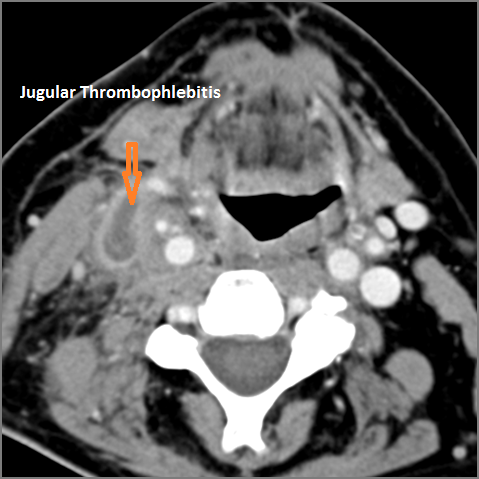

|

There is evidence of thrombus, thrombophlebitis or other occlusive or inflammatory process of the jugular vein or smaller jugular venous tributaries. |

No | NA |